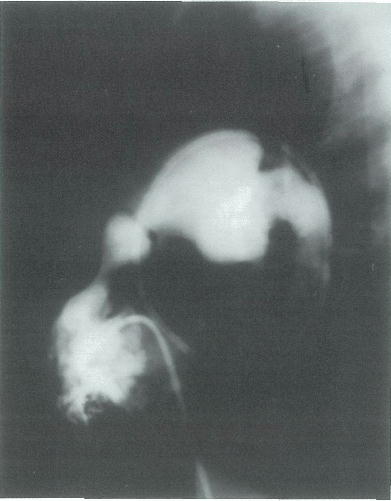

5歳の男児。心臓カテーテル検査を目的に入院した。正期正常分娩で出生した。1か月時の健康診査で心雑音を指摘され,その後は外来で半年に1度経過観察されていた。運動時に軽い呼吸困難を訴える。身長 102cm,体重 15kg。体温 36.7℃。呼吸数 24/分。脈拍 84/分,整。血圧 98/62mmHg。呼吸困難とチアノーゼとを認めない。胸骨左縁第2肋間を最強点とする3/6度の粗い収縮中期雑音を聴取する。呼吸音に異常を認めない。腹部は平坦,軟で,肝・脾を触知しない。心臓カテーテル検査所見:主肺動脈圧 22/10mmHg,右室圧 75/10(拡張終期)mmHg,大動脈圧 92/58mmHg,左室圧 94/8(拡張終期)mmHg,Qp/Qs 1.0。右室造影写真側面像を別に示す。

対応として適切なのはどれか。

b 経皮的バルーン弁形成術